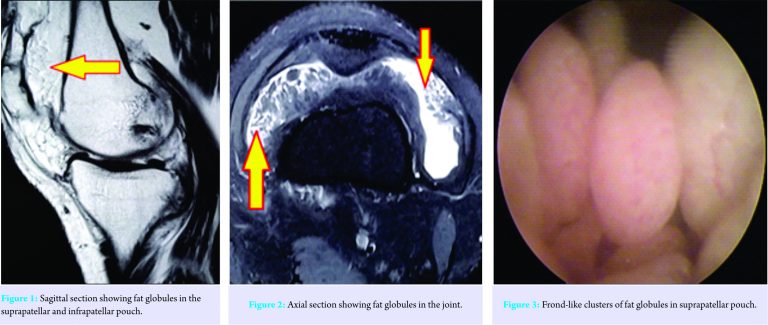

Our patient was a 29-year-old male patient (BMI – 21.6) who presented with persistent RT knee pain over the period of 8 months. It was associated with occasional mechanical symptoms such as popping and locking while performing daily activities. The patient denied of any history of trauma and had been treated by a general practitioner with nonsteroidal anti-inflammatory drugs for the pain without any favorable outcome. On examination, the knee was found to be swollen with noticeable fullness of suprapatellar pouch. On palpation, there was no specific tender point or the presence of fluid in the joint. Examination revealed no instability with varus and valgus stress testing, negative posterior-anterior drawer tests, and negative Lachman and McMurray’s tests. He had free active knee range of motion without crepitus or clicking with normal patellar tracking. X-rays showed normal joint space and no abnormal soft tissue shadows, fractures, or osteochondral lesions. The MRI images showed high signal intensity villous or nodular foci on both T1- and T2-weighted images which were indicative of fat globules (Fig. 1 and 2).

They were predominantly found in huge number in suprapatellar pouch, and no other ligamentous or meniscal defect was found. Since the patient had clear MRI findings consistent with synovial lipomatosis, he was posted for arthroscopic synovectomy after all routine pre-operative investigations, which were found to be normal. On arthroscopy, a large number of fat globules was found in suprapatellar pouch and some in the medial and lateral gutter. They had typical “frond-” like appearance and found in multiple clusters (Fig. 3 and 4). There was the absence of any ligamentous, meniscal, or osteochondral lesions. Arthroscopic synovectomy and extensive debridement of polyp-like fat projections of the right knee was performed. Approximately 40 cc of lobulated globules were removed, and some were sent to histopathology (Fig. 5). The reports confirmed the presence of benign synovial tissue and fragments of adipose tissue present beneath the synovial surface (Fig. 6). The patient was started with an active range of motion exercises from the first day and was discharged on the 5th day. On 1-year follow-up, the swelling was dramatically reduced, and the patient was free of pain and devoid of all mechanical symptoms.